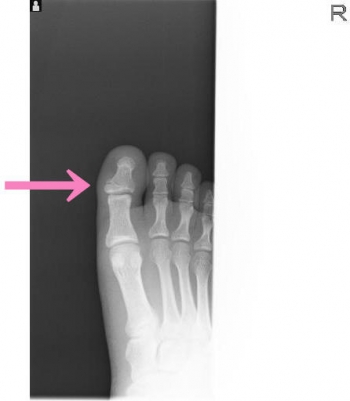

今日、ご紹介するのは、足・足指 足指骨骨折についてご紹介していきます。

足・足指 足指骨とは

足指骨は、四肢動物の後肢の先端部にある、足の指を構成する骨の集合です。

基節骨・中節骨・末節骨で構成される骨の集合で、動物の手足において、指に相当する部分を構成している。

足指骨骨折

足指骨骨折の発生機序

直達外力では、重量物の落下が多い

介達外力では足尖から衝撃が加わり発生。

足指骨骨折の症状

骨折指の腫脹

限局性圧痛

骨長軸からの軸圧痛

荷重痛

異常可動性

軋轢音

基節骨骨折、とくに第1、2指は足底凸の変形が残り、荷重および歩行障害が起こりやすいです。